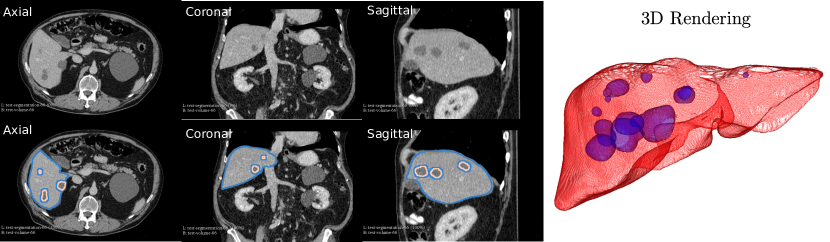

Refer to caption

Figure 7: The example liver lesion segmentation results from 3D AH-Net. The segmented contours of liver (blue) and liver lesion (pink) are overlaid on 3 slices viewed from different orientations (Axial, Coronal and Sagittal). The segmentations are rendered in 3D on the right.

The performance of AH-Net is listed in Table 5, together with other six top-ranked submissions retrieved from the LITS challenge leaderboard. These submissions employ various types of neural network architectures: 2D, 3D, 2D-3D hybrid, and model fusion. Two evaluation metrics are adapted: (1) Dice Global (DG) which is the dice score combining all the volumes into one; (2) Dice per Case (DPC) which averages of the dice scores of every single case. The Dice score between two masks is defined as DICE(A,B)=2|AB|/(|A|+|B|)𝐷𝐼𝐶𝐸𝐴𝐵2𝐴𝐵𝐴𝐵DICE(A,B)=2|A\cap B|/(|A|+|B|). Our results achieve the state-of-the-art performance in three of the four metrics, including the dice global score of the lesions, dice global and dice per case score of the livers, which proves the effectiveness of AH-Net for segmenting 3D images with diverse anisotropic resolution. Some example results are shown in Fig.7.

Three example volumes are selected from the test image set to demonstrate the effectiveness of our proposed network in Fig. 24, Fig. 25 and Fig. 26. Although we do not have the groundtruth label maps for the testing images, the liver boundaries and the presence of lesions can be visually inspected. The liver lesions normally appear as a dark region within the liver. Without sufficient 3D context, MC-GCN tends to generate false positive regions at the structure boundaries, especially under low image contrast. From the sagittal and coronal views, it is visible that MC-GCN could not generate the correct boundaries close to the top or the bottom of the lesion. By considering the consistency between slices, 3D AH-Net can segment the structures in 3D correctly, although the feature extraction network is transferred from a 2D network. The jagged boundary in the sagittal and coronal view is due to the low resolution in the z direction.